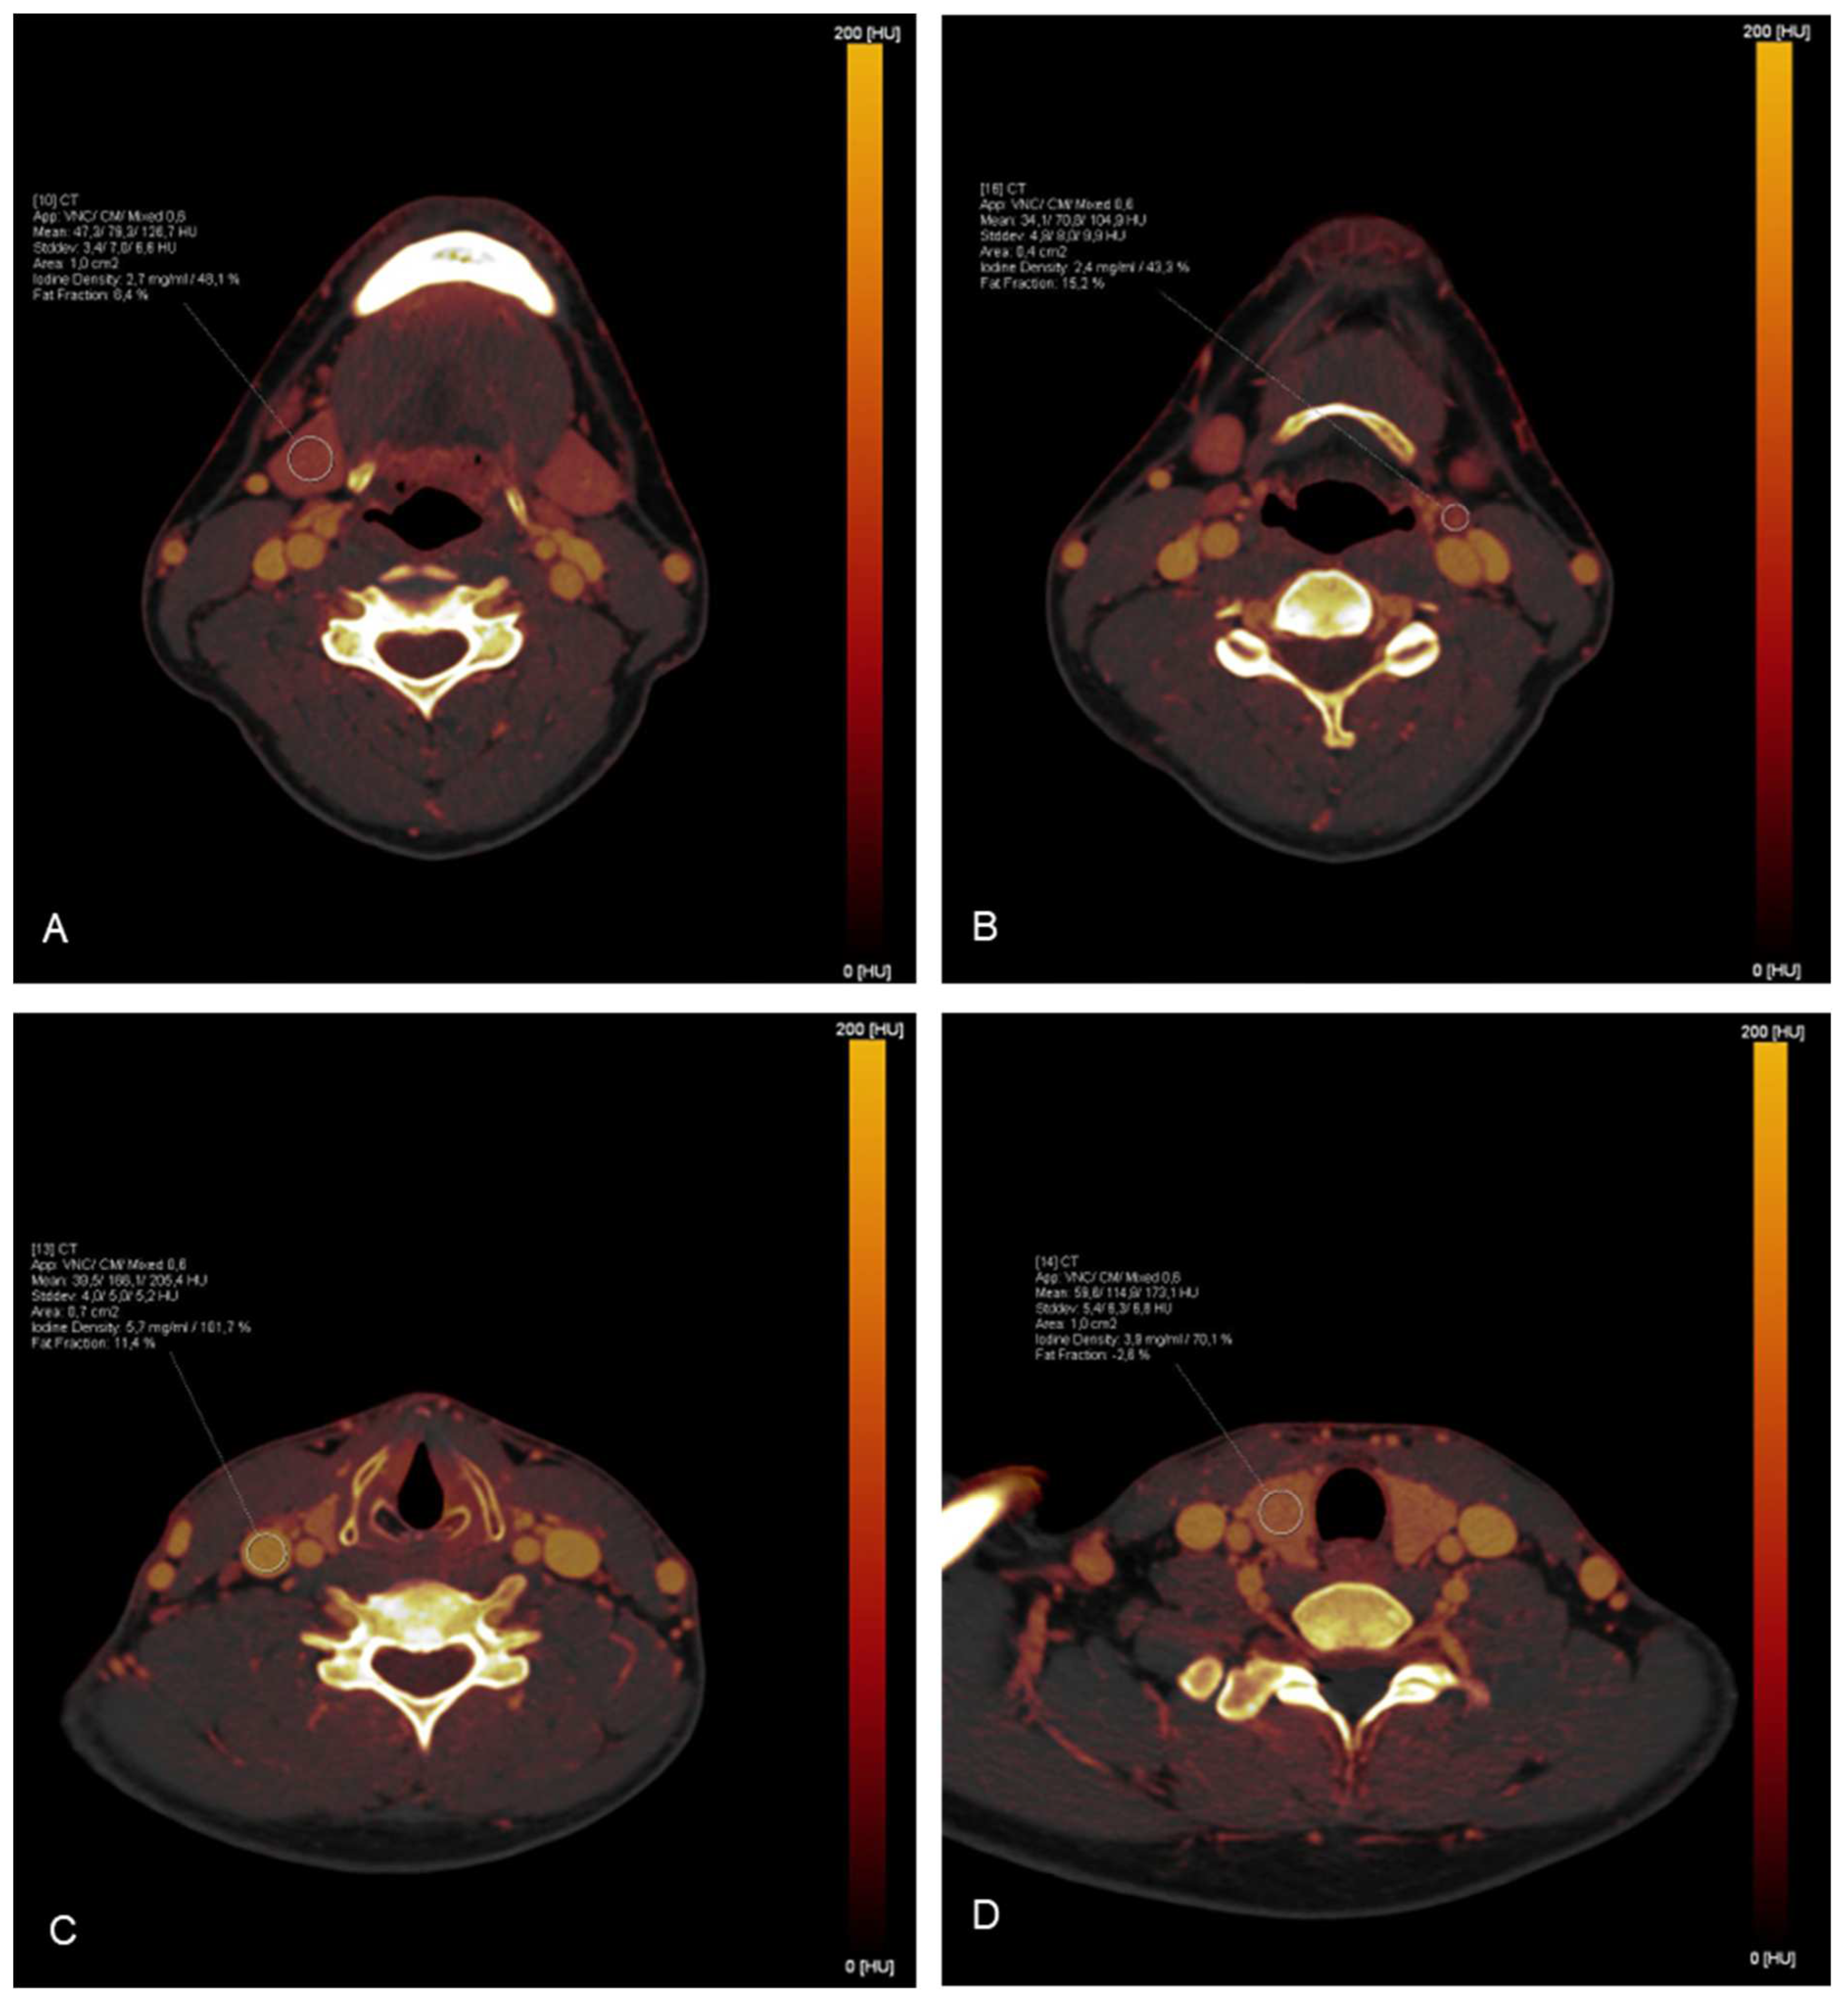

2.3. Iodine mapping and uptake measurements